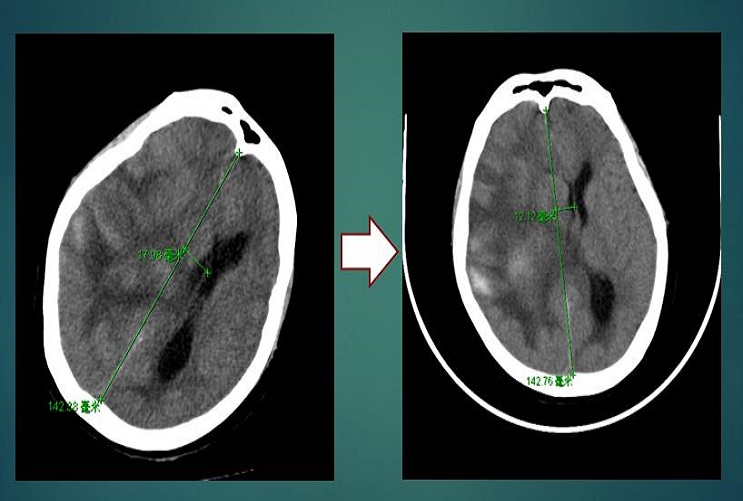

2021.05.12(用药7天):使用脑血疏口服液1周后,患者情况逐渐好转,右侧瞳孔较前缩小,刺痛肢体可屈曲,CT示血肿明显吸收,中线移位情况好转,17.98 mm→12.12 mm,GCS 3分→6分。

2021.05.12(用药7天)CT

2021.05.12(用药7天)CT示中线移位情况好转